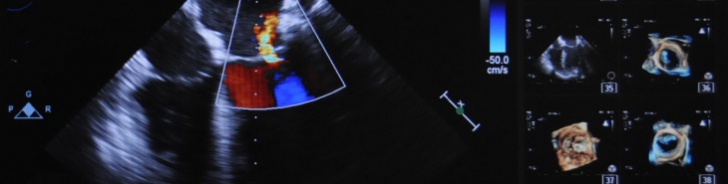

- Valve Replacement in Median Sternotomy or Mini-Thoracotomy

- Heart Valve Reconstruction also Minimally Invasive

- Catheter Intervention Replacement (TAVI)